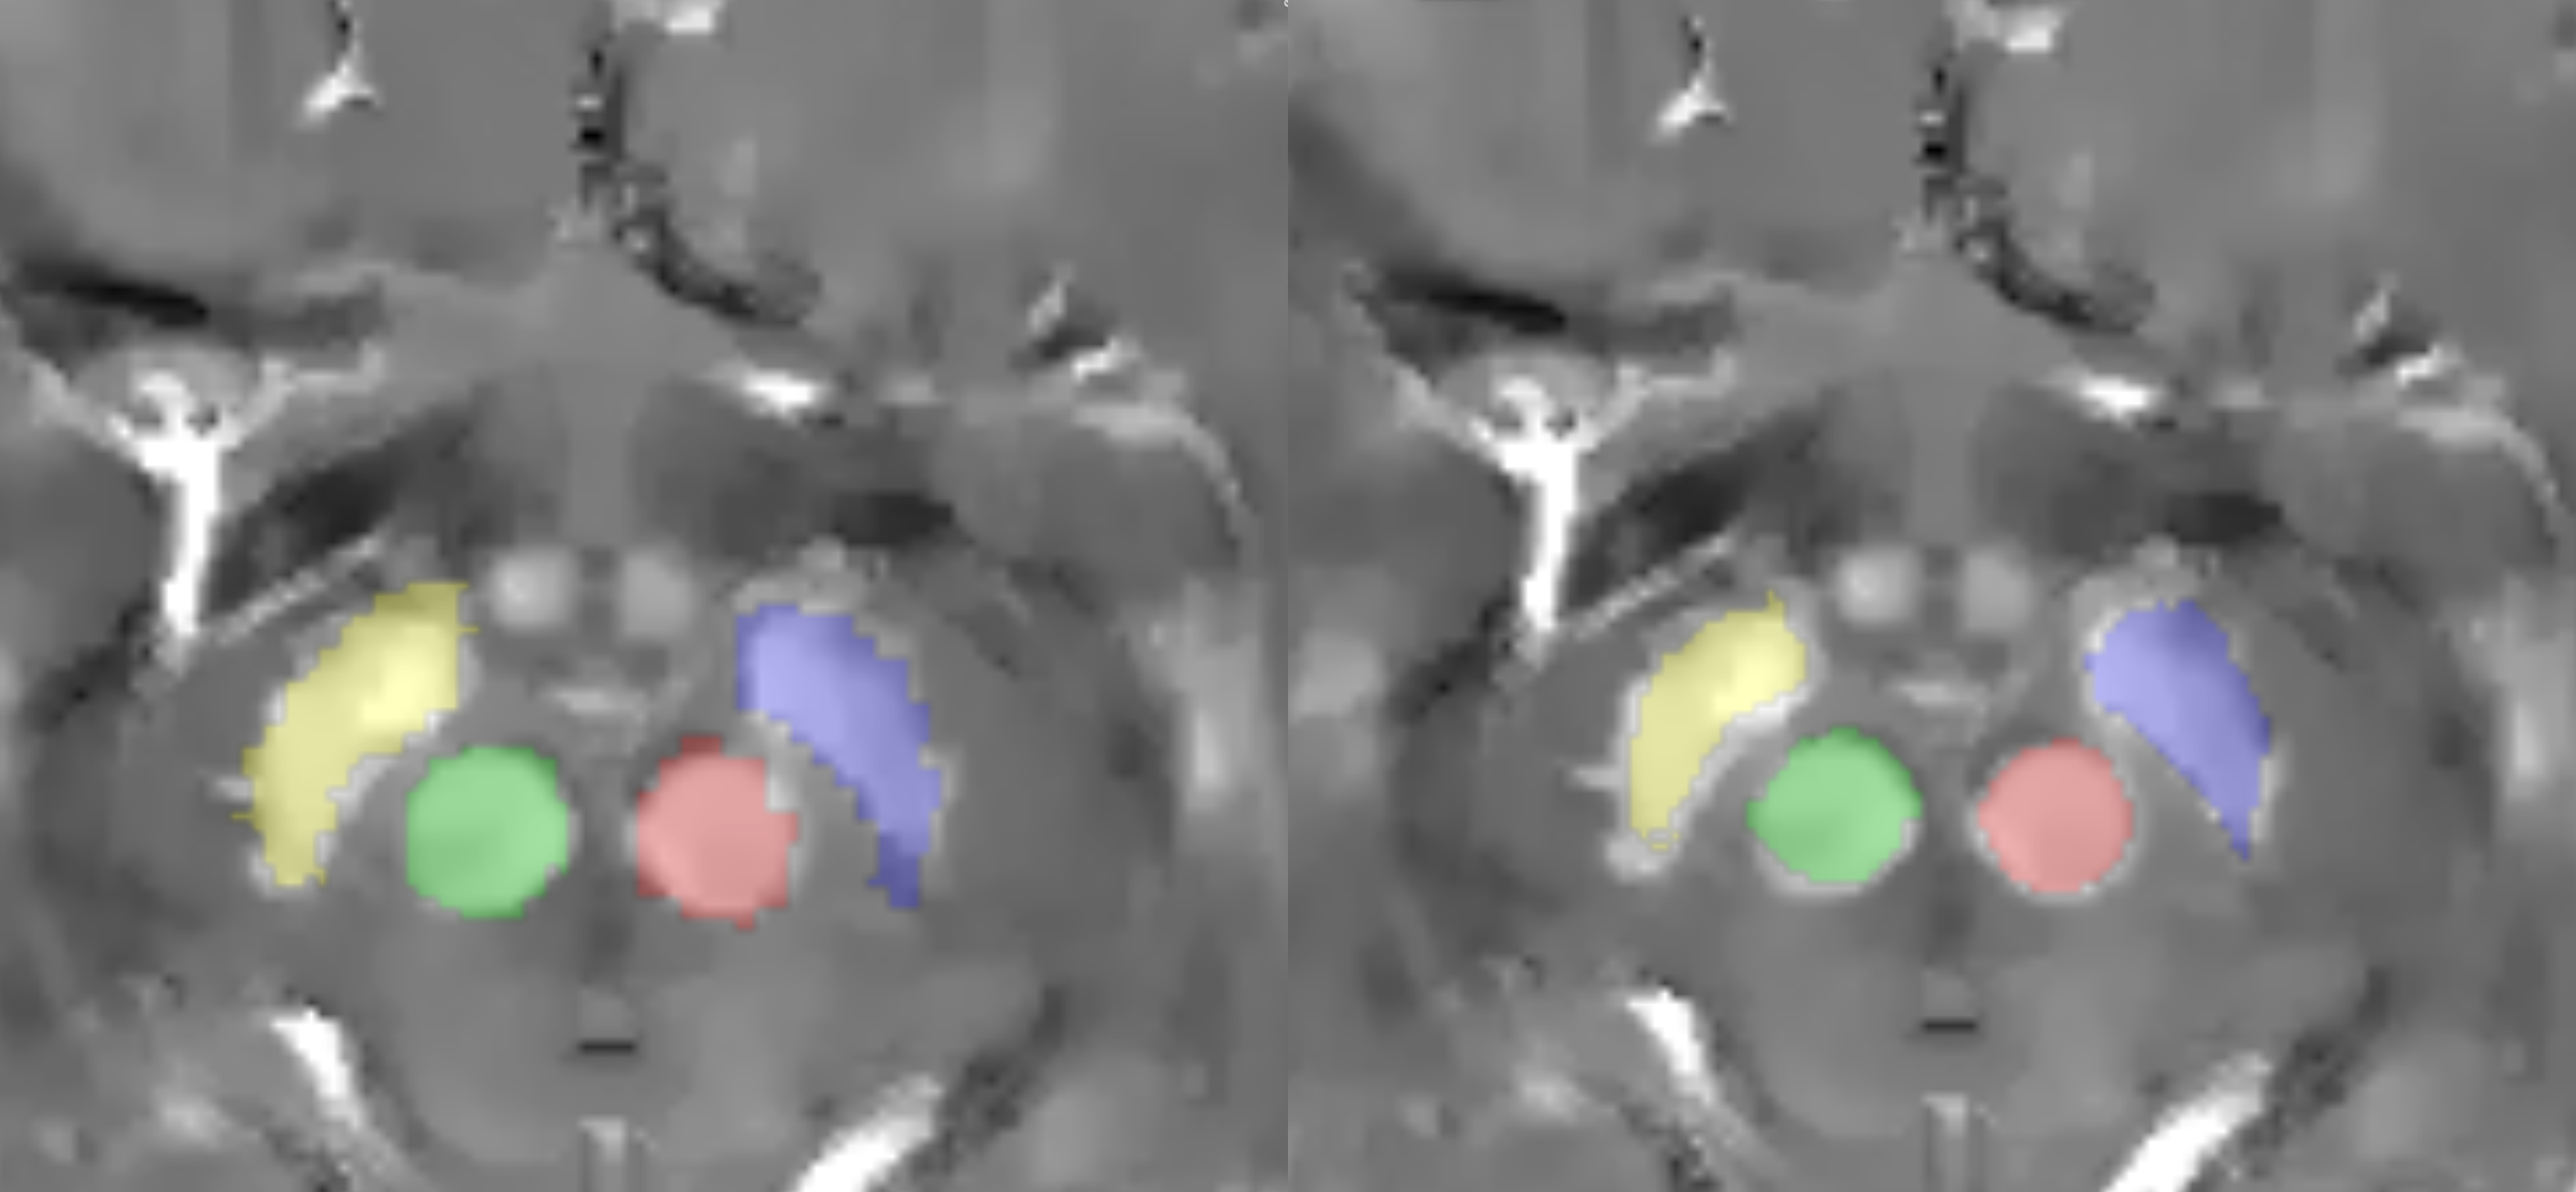

Results: The proposed atlas shows improvement over the McGill atlas in segmentations [figure2]. Applying transforms to relaxation and susceptibility map generates atlases in [fgure3]. The DN visualization, STN/SN delineation and GP/PUT contrast is improved in the susceptibility maps χ, χ+ [figure4] compared to structural T1w. White matter tracts on negative source χ– and myelin fraction v are visible [figure5].

Masks via McGill atlas and proposed method.